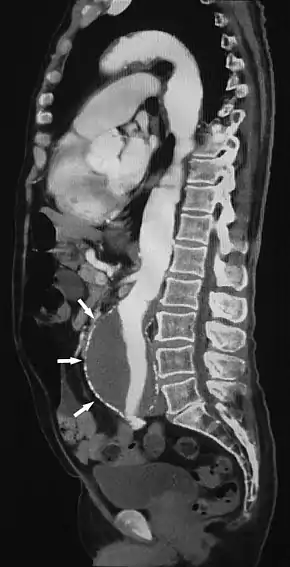

| Computed tomography angiography | |

|---|---|

![]() Sagittal thin slice of a computed tomography angiography abdominal aortic aneurysm (AAA) (arrows) | |